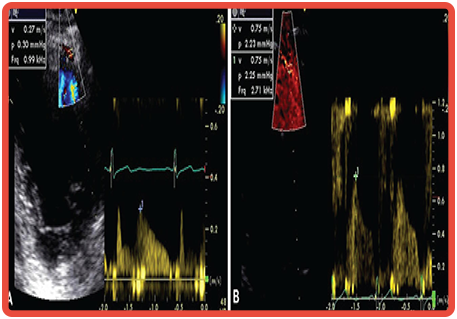

18 - Análise de Fluxo Coronariano

Avaliar o fluxo coronário e ramos buscando determinar a reserva coronária (RC). Geralmente realizado na artéria descendente anterior e menos frequentemente nas artérias circunflexa e coronária direita.

COMO É FEITO![]()

Durante ecocardiografia com estresse o especialista titulado em ecocardiografia obtém o fluxo coronariano e faz a interpretação.

INDICAÇÕES![]()

1) avaliação de lesões intermediárias na descendente anterior;

2) estimativa do fluxo coronário pós-infarto e o prognóstico;

3) avaliação de resultados e predição de reestenoses pós-angioplastia;

4) determinação de resultados cirúrgicos;

5) avaliação da microcirculação;